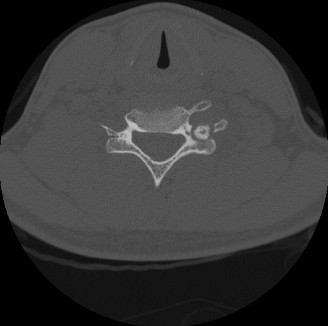

Computed Tomography

A multi-detector Computed Tomography (CT) scan of the distal femur without intravenous contrast was subsequently performed. The primary indications for this modality were to better characterize the lesion's internal bony architecture, meticulously evaluate the integrity of the lateral cortex, and delineate the precise three-dimensional extent of the tumor for preoperative templating.

The CT scan confirmed an intramedullary, eccentric lesion with a well-defined, thick sclerotic border, originating squarely in the metaphyseal region. It demonstrated significant endosteal scalloping and cortical expansion, leading to marked thinning of the lateral femoral cortex; however, the cortex remained continuously intact without frank macroscopic breach. The nidus, highly characteristic of osteoblastoma, was identified as hyperdense relative to surrounding marrow, exhibiting heterogeneous attenuation and subtle, stippled internal calcifications that were not readily apparent on plain radiography. Critically, the CT provided invaluable detail regarding the spatial relationship of the lesion to the closed physis and the articular surface, confirming that the tumor was entirely extra-articular and metaphyseal, thereby informing surgical planning for intralesional curettage and marginal excision.